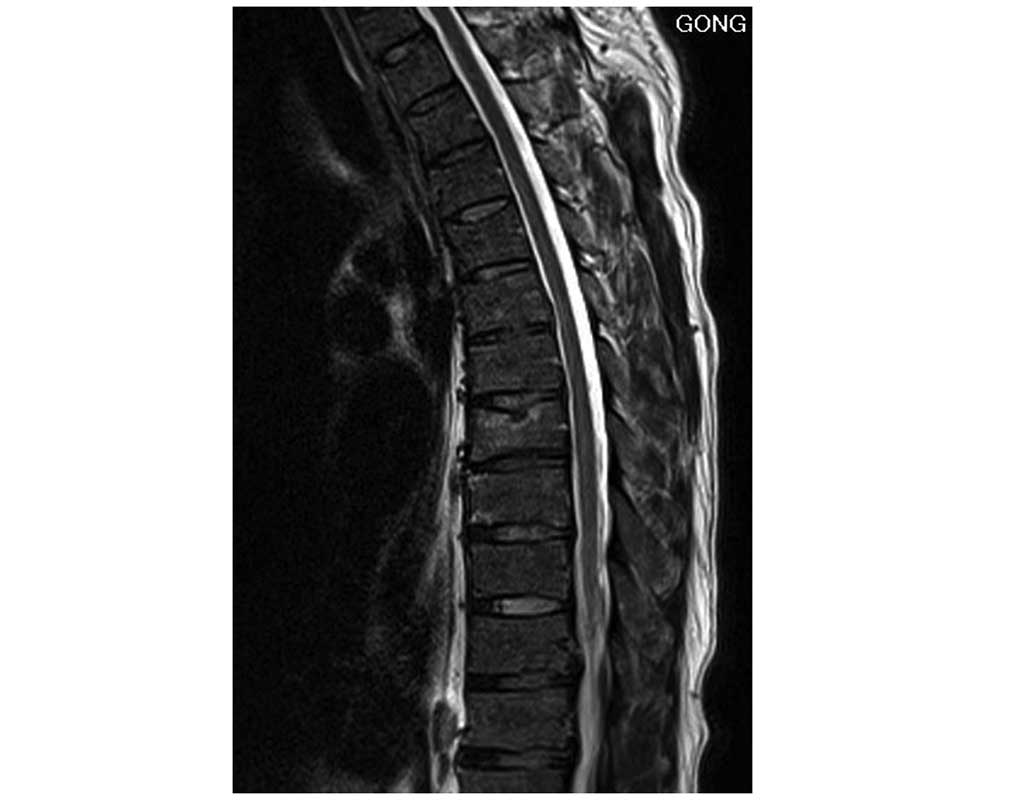

The present study reports the case of an adult patient with non-traumatic acute paraplegia following a computed tomography (CT)-guided automated cutting needle biopsy (ACNB). Multiple nodules and masses were revealed on performing chest radiography and CT on a 45‑year‑old man. In order to make a pathological diagnosis, a CT‑guided biopsy using an automatic cutting needle was performed. However, 10 min after the biopsy, a weakness of the lower extremities occurred, and the patient collapsed to the ground, albeit with clear consciousness. Spinal magnetic resonance imaging (MRI) performed subsequently revealed no abnormal findings in the spinal cord. An MRI performed 24 h later, however, revealed swelling of the thoracic spinal cord and a high‑signal‑intensity lesion in T2‑weighted images at the level of T7, T8 and T9. The patient subsequently received hyperbaric oxygen therapy for a few days, and rehabilitative treatment over the course of a few weeks. At 6 months following the biopsy, the patient was unable to walk, although the patient could stand for 10 min and defecate independently. Currently, the patient remains active in daily life, in spite of confinement to a wheelchair. The present case study was reported to raise the awareness of the possibility of spinal cord ischemia and acute paraplegia following a CT‑guided ACNB of the lungs. The mechanism underlying spinal cord ischemia remains to be fully elucidated, although is thought to be multifactorial, involving air embolism.

Figure 1

Figure 2